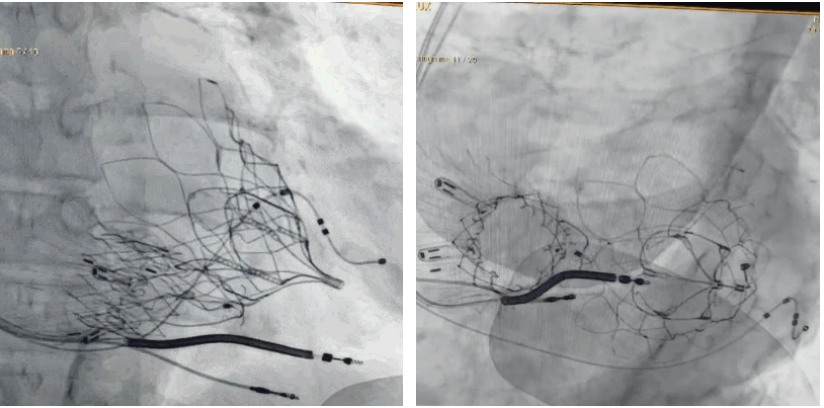

術(shù)后DSA顯示Lux-Valve Plus與Tendyne和ICD無(wú)相互影響

手術(shù)在全麻狀態(tài)下進(jìn)行。術(shù)者采用經(jīng)右側(cè)頸靜脈入路的方式將輸送器送入患者心臟內(nèi),在TEE及DSA引導(dǎo)下調(diào)整輸送器頭端角度,使得輸送器與三尖瓣瓣環(huán)平面垂直。在輸送器進(jìn)入右心室后釋放室間隔錨定裝置,而后釋放瓣葉夾持件(2個(gè)耳片結(jié)構(gòu))成垂直狀態(tài)。在TEE及DSA確定夾持件固定至三尖瓣葉根部且位于右室側(cè)后釋放人工瓣心房側(cè)盤片。隨后調(diào)整瓣膜同軸性以及室間隔錨定件位置(貼合室間隔),前推藏針管并固定,進(jìn)而釋放室間隔錨定裝置,并再次確認(rèn)瓣膜位置、穩(wěn)定性及同軸性,合攏輸送鞘后撤出輸送器,完成LuX-Valve Plus人工三尖瓣瓣膜的植入,僅殘余微量瓣周漏。且經(jīng)手術(shù)中心電生理團(tuán)隊(duì)評(píng)估,病人的起搏器和ICD功能沒(méi)有受到影響。